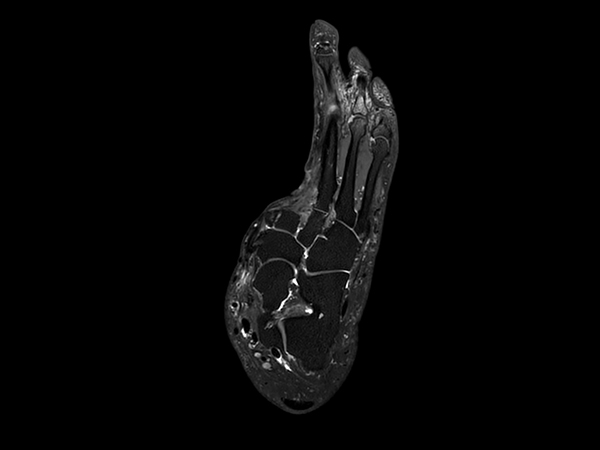

Ankle/Foot imaging post-amputation

Patient with partial amputation of the foot

3D VIEW PDw SPAIR - Axial reformat